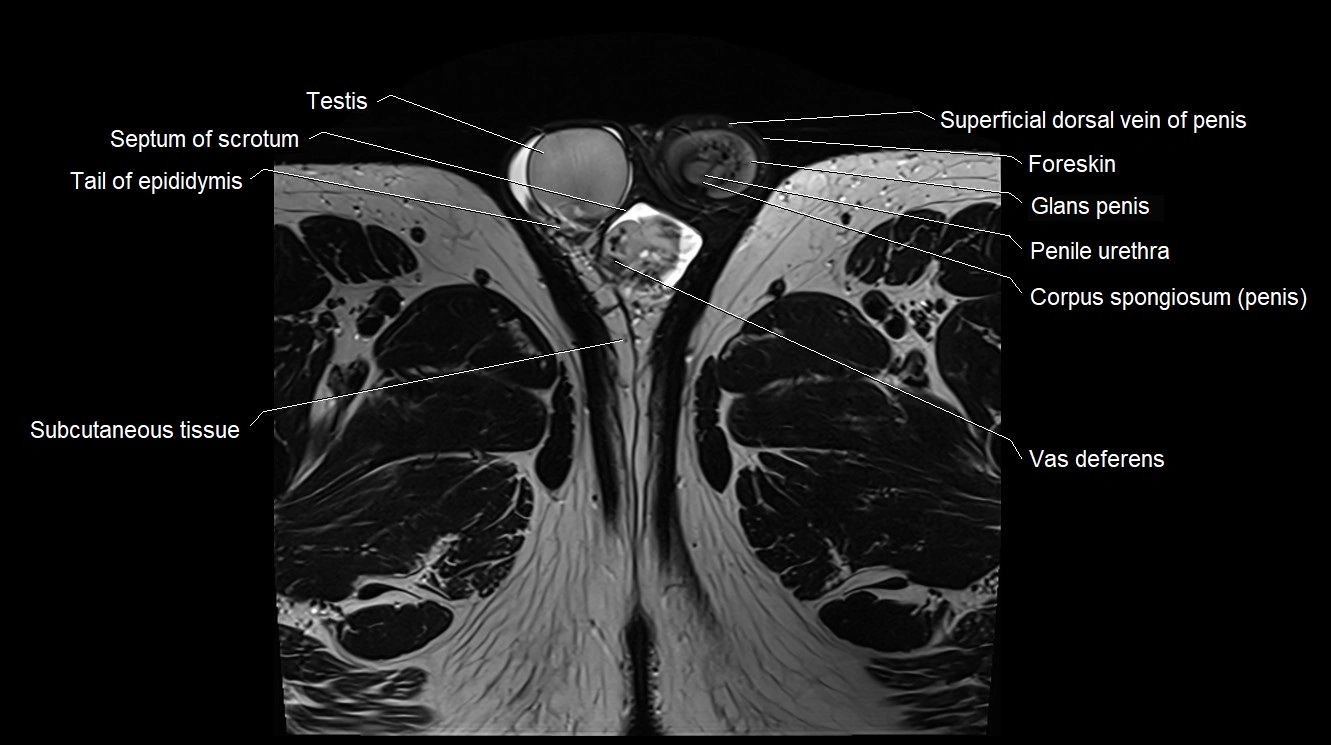

MRI image